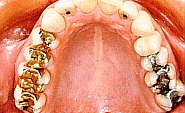

Auf diesem Bild sind Amalgam- und Gold-Füllungen zusammen in einem

Mund zu sehen. Amalgam-Füllungen sind hier sogar an den seitlichen

Frontzähnen.

Dieses Bild dient nur zur Illustration zweier verschiedener Füllungs-Arten

Aus biologischer Sicht ist jedoch die Anwesenheit von Gold und Amalgam

zusammen im Mund abzulehnen. Durch den Speichel als flüssigem Medium

entsteht eine Batterie, in der die Quecksilber-Bestandteile in Lösung

gehen und somit verschluckt werden können.

Saure und auch süsse Getränke verstärken durch eine Reduzierung

des Speichel-pH-Werts diesen negativen Effekt.